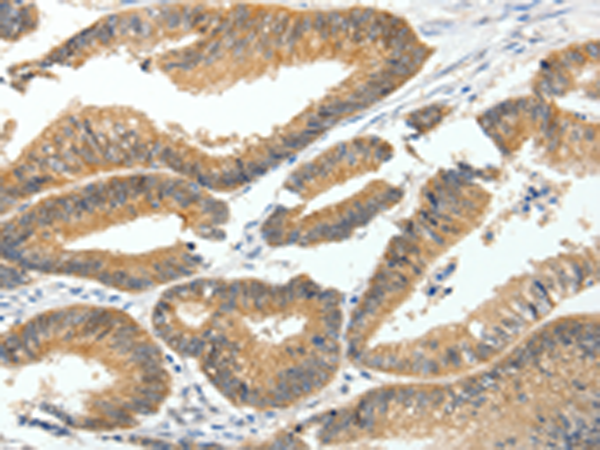

分类: 科研抗体货号: P00466别名: CD29; FNRB; MDF2; VLAB; GPIIA; MSK12; VLA-BETA应用: WB,IHC反应种属: Human, Mouse, Rat